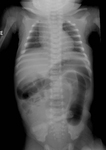

Radiografia abdominal de neonato com padrão fecal anormal e constipação. Os cólons transverso e descendente dilatados são sugestivos de doença de Hirschsprung